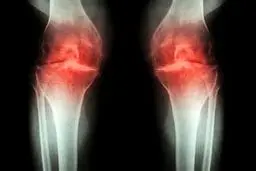

آرتروز :

روش درمان آرتروز با شناسایی سیگنال درد

استئوآرتریت میتواند یک بیماری ناتوان کننده باشد و حرکات…